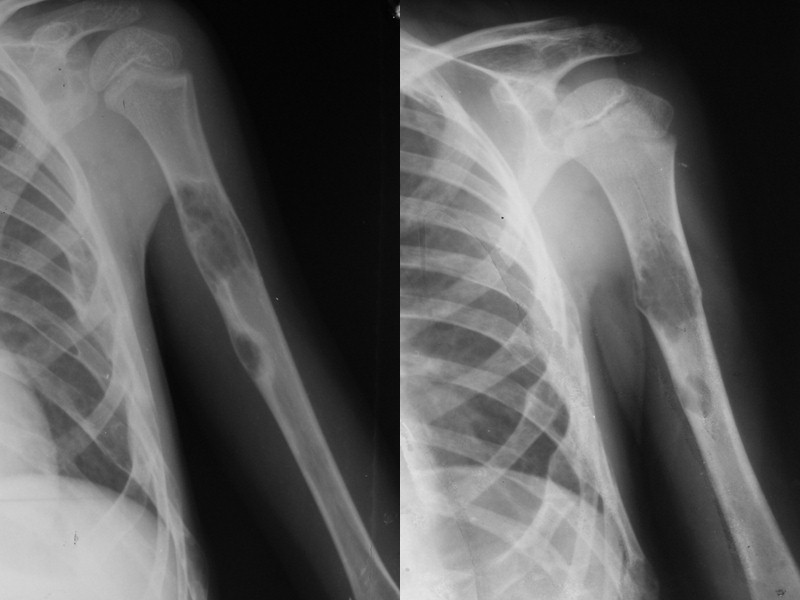

Солитарная костная киста Выявляется в возрасте от 5 до 25 лет Одиночная, как исход ОК, фиброзной дисплазии, травмы или воспаления Преимущественная локализация – проксимальный метадиафиз длинных трубчатых костей (плечо, бедро) Не переходит через ростковую зону, отодвигается к диафизу с ростом кости Располагается по центру, овоидной формы, дает вздутие и истончение кортикального слоя, имеет четкую границу от окружающей кости Структура – крупно ячеистая Часто осложняется патологическими переломами, после чего и выявляется Часто рецидивирует (60%) после оперативного лечения